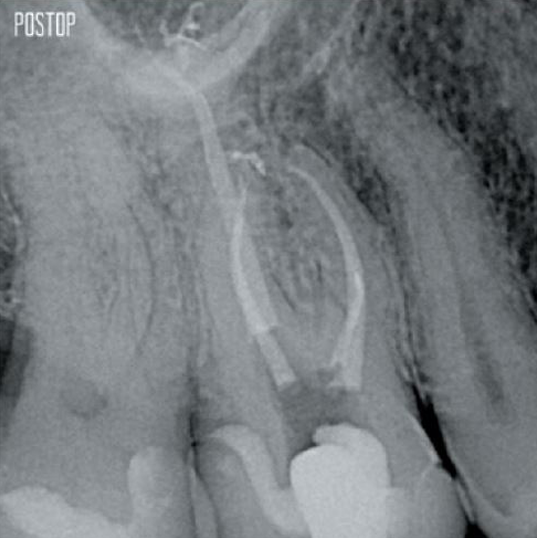

Photos courtesy of Dr. Ahmed Salman

More dentin preserved. Appropiate shaping, irrigation, and obturation ensured.

The union of the file geometry, regressive tapers and the slim, highly-flexible wire enables efficient root canal treatment while removing only dentin where clinically needed.1

TruNatomy® preserves as much dentin as possible1 and offers a complete solution including matching irrigation and obturation.

Yes, the TruNatomy Conform Fit® gutta-percha points are designed to perfectly match the preparations made with TruNatomy files and ensure an optimal obturation.